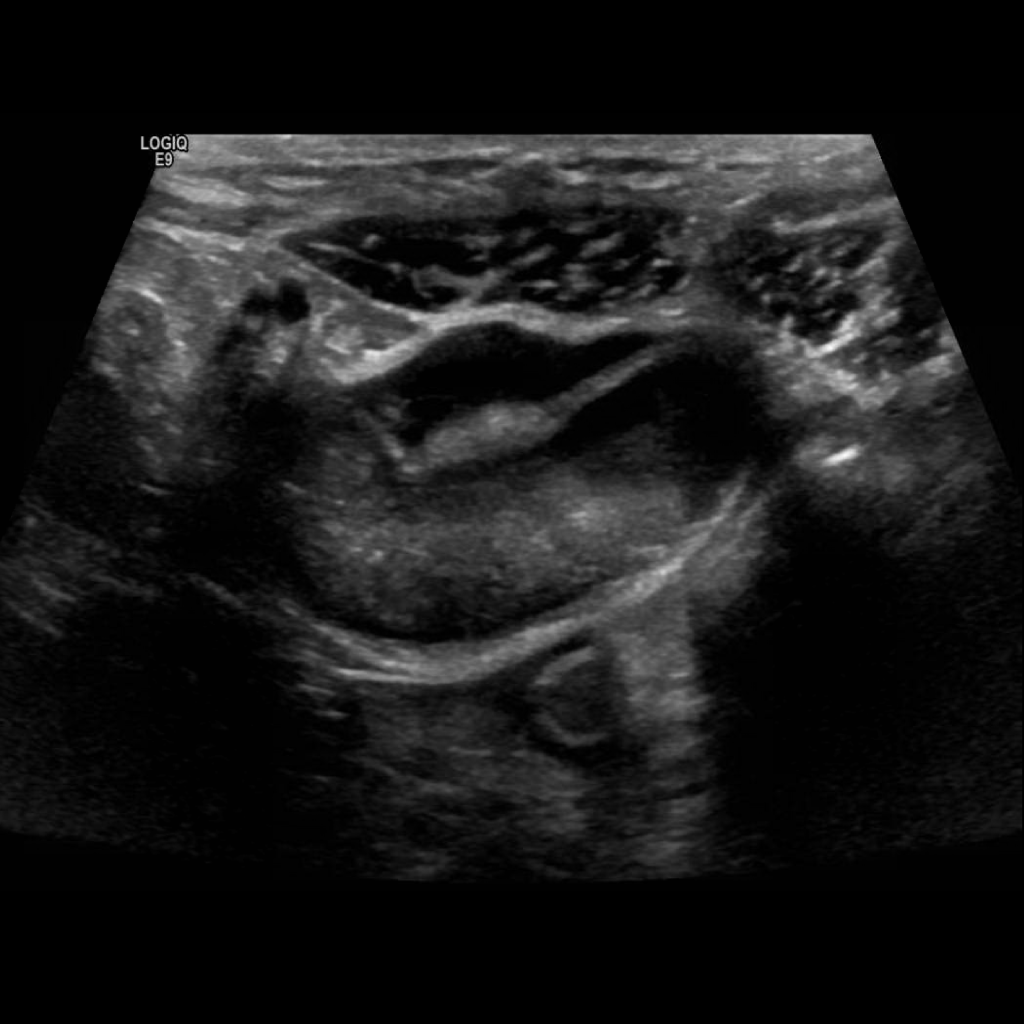

Appendicitis 2

Large appendix with appendicolith and hyperemia.